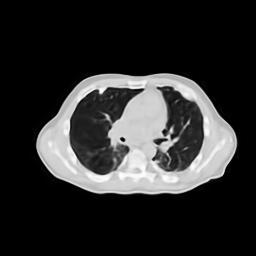

IV-F Real CT Reconstruction

To further verify the effectiveness of the RBP-DIP framework, real CT data from the Finnish Inverse Problem Society [49, 50] was used to validate our algorithm. The few-view and limited-angle reconstruction results are shown in Figure 12. Due to the lack of available training sets, pre-trained models were not included in the experiments. Different from the previous experiment, data from Finnish Inverse Problem Society is highly noisy. However, it is still evident that the RBP-DIP outperforms all other algorithms in all experiments, even under high noise and highly ill-posed conditions.

(a) Reference

8.41dB/0.34

(b) ASD-POCS

12.77dB/0.31

(c) DIP

14.59dB/0.45

(d) RBP-DIP